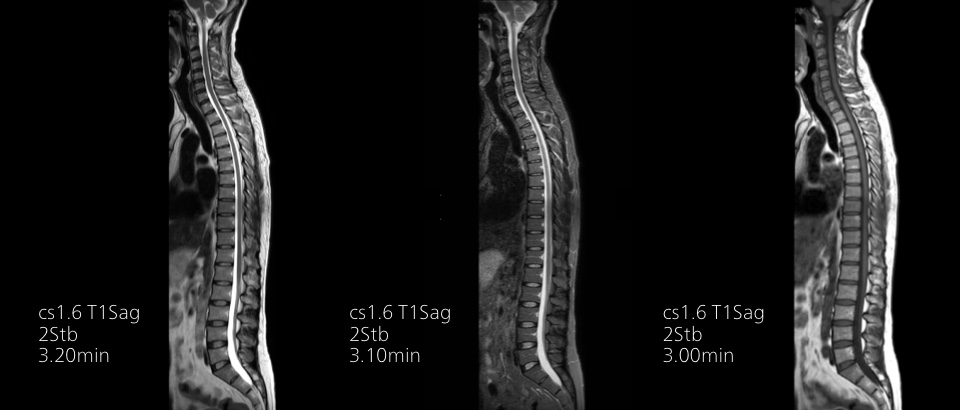

Convierta las imágenes en respuestas hasta un 50% más rápidas

Ponga el tiempo de su lado con Compressed SENSE para reducir el tiempo de exploración hasta en un 50% 2 con una calidad de imagen prácticamente igual. Cree imágenes excepcionales de resonancia magnética con una resolución un 60% más alta para un diagnóstico seguro.

16:30 minutos

Convencional

8:00 minutos

Compressed SENSE